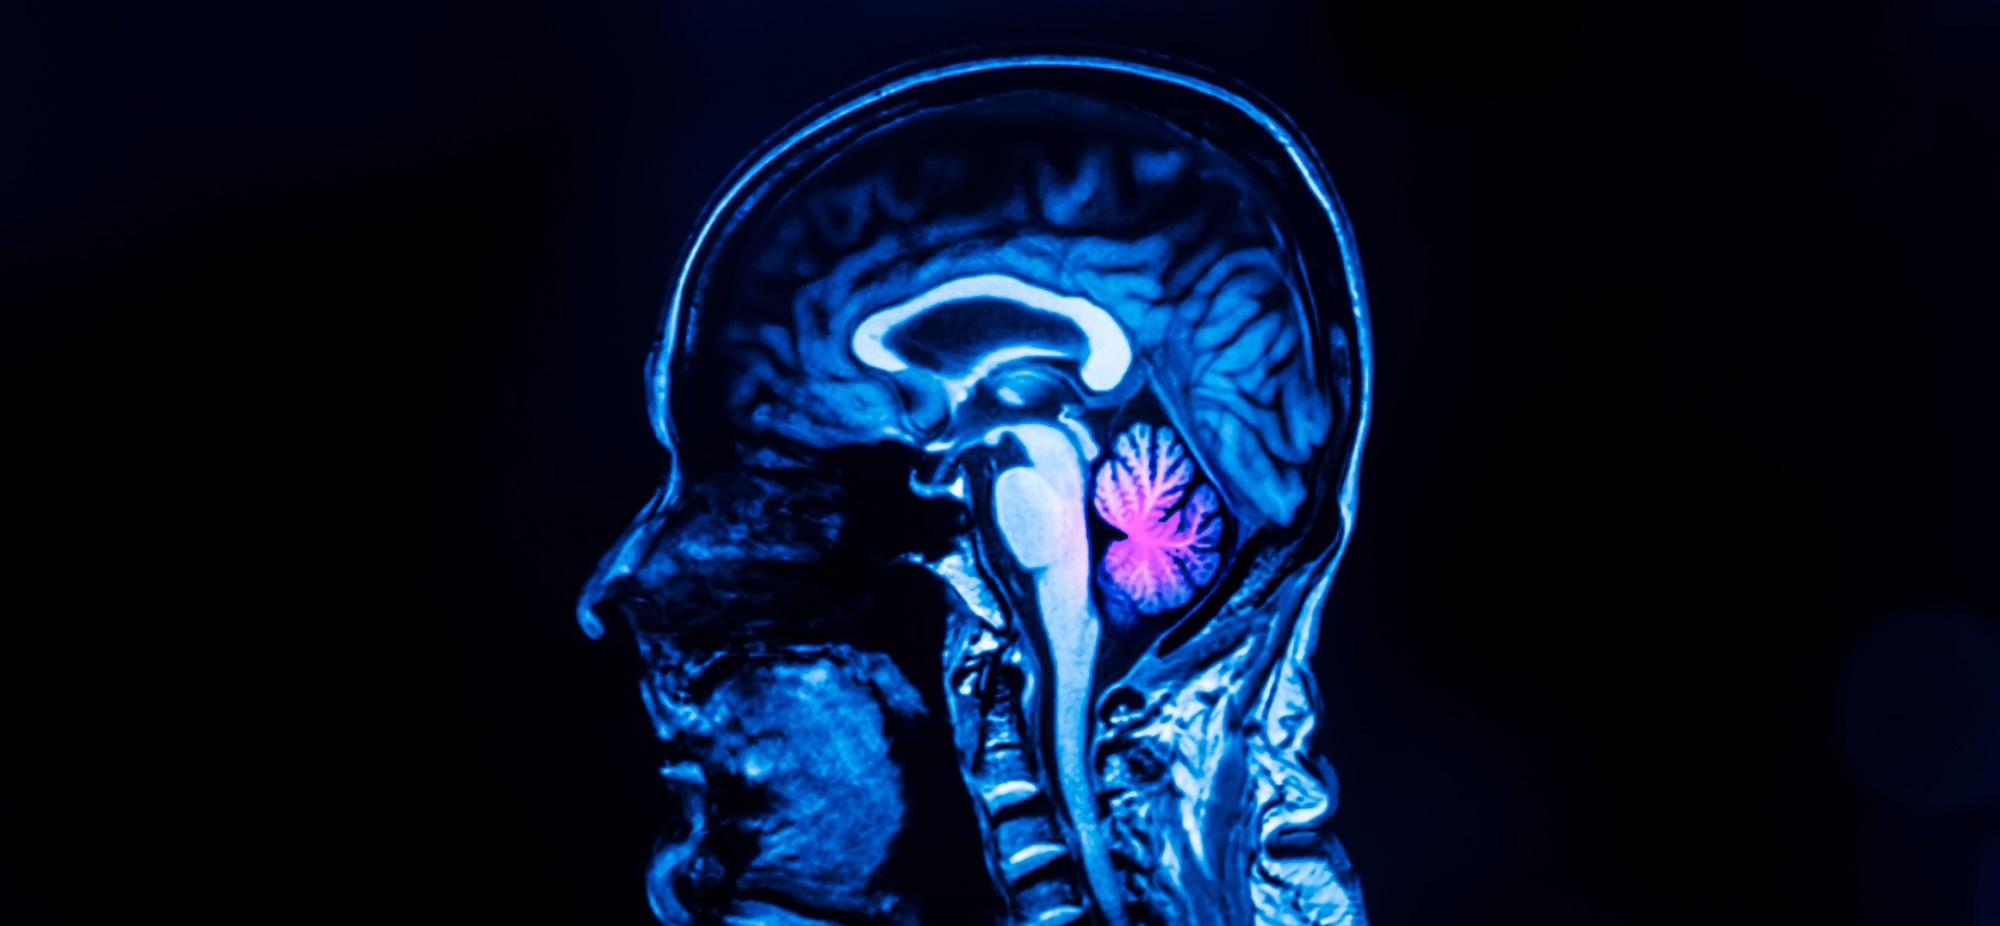

Cerebellum

Cerebellar agenesis is a condition in which the normal formation of the hindbrain is disrupted. Image Credit: Peter Porrini/Shutterstock.com